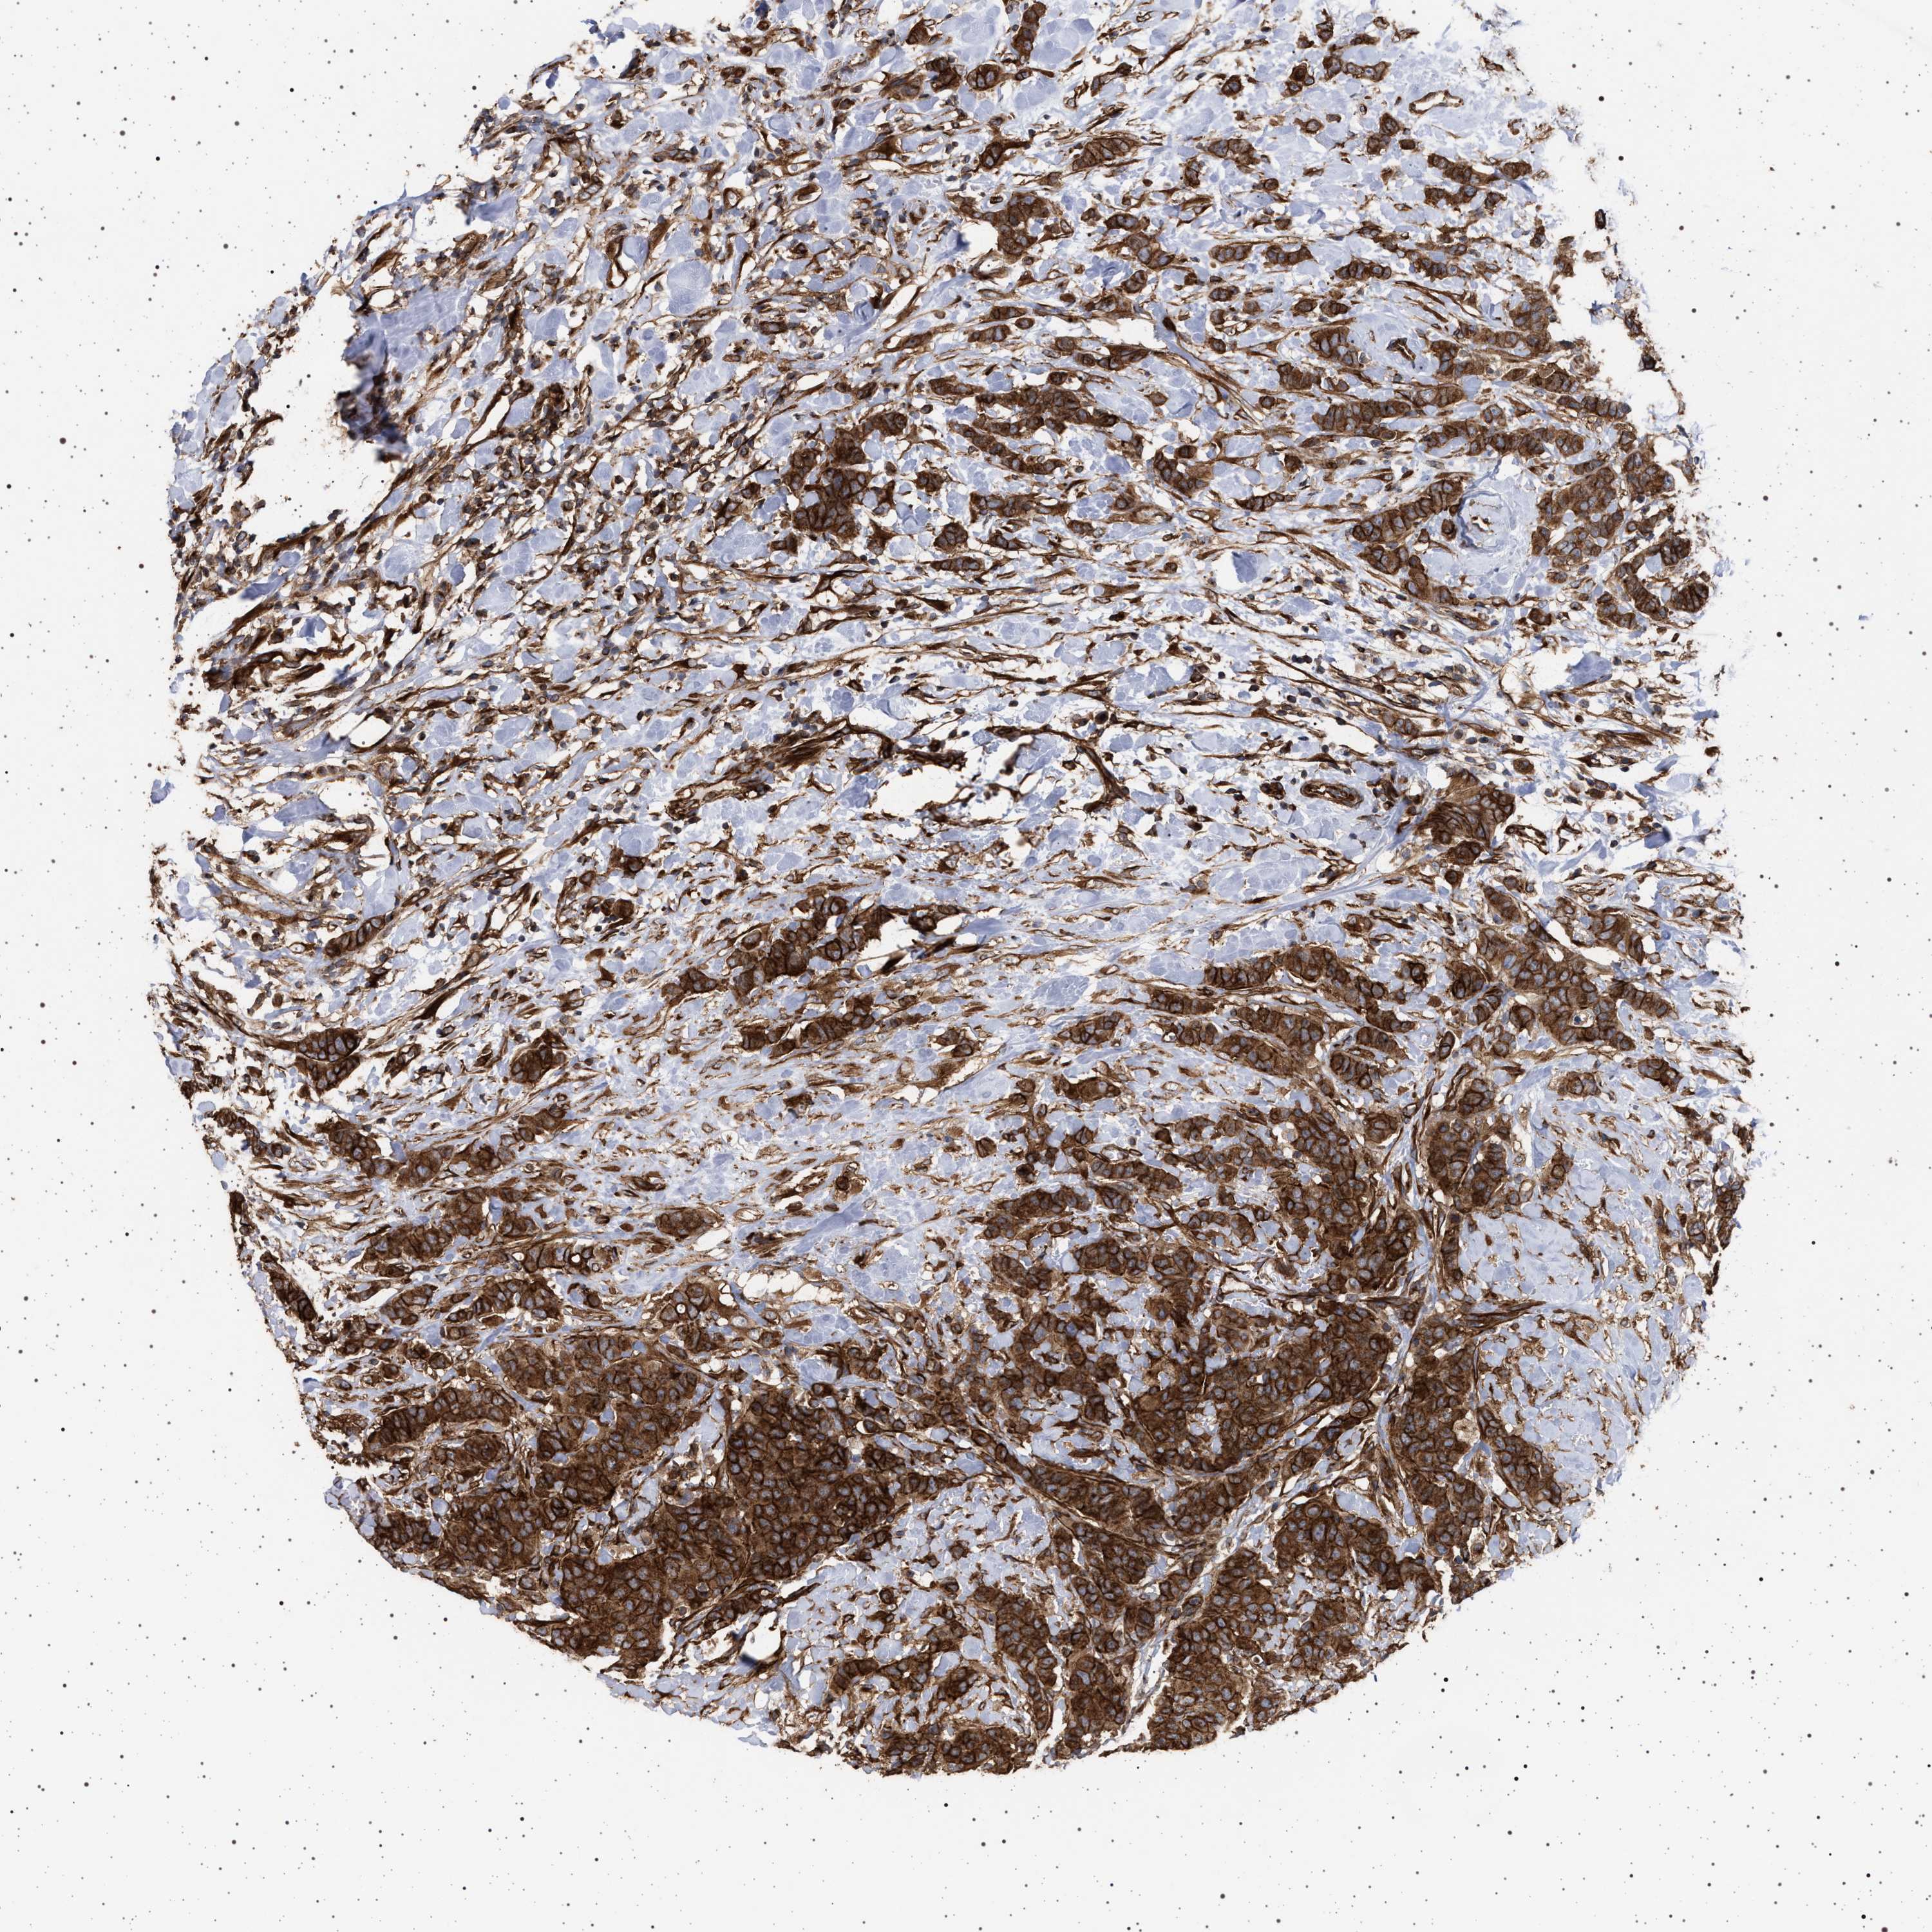

CANCER BREAST CANCER Show tissue menu

BRCA TCGA BRCA VALIDATION PROTEIN EXPRESSION